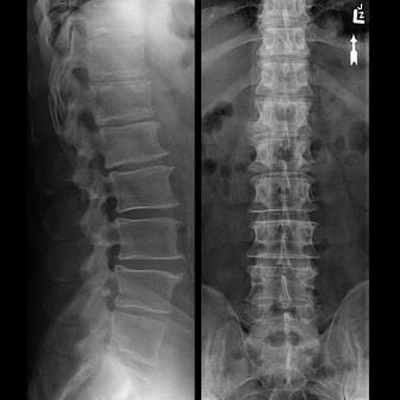

Рентгенограмма позвоночника при сколиозе

Рентген грудного отдела делаться в 2-ух проекциях (в прямой и боковой), в положении лёжа. А, в случае искривления, для оценки разницы в отклонении позвоночного столба, делаются снимки в одной проекции, стоя и так же лёжа – это даёт возможность судить о стабильности или нестабильности позвоночника.

На рентгенограмме грудного отдела позвоночника врач-рентгенолог видит и оценивает:

- состояние тел позвонков – в норме не должно быть трещин, смещений, изменения высоты между позвонками, изменений формы тел

- патологии (есть или нет) в межпозвоночных дисках

- места прикрепления рёбер к позвонкам

- форму позвоночного столба

При диагностировании степени сколиоза назначается функциональная рентгенография грудного отдела. Для этого делается два снимка в прямой проекции:

- Стоя – пациент становится спиной к приёмнику рентген-аппарата, луч центрируется на среднюю область груди, делается снимок.

- Лёжа – делается так же, как и обычный снимок в прямой проекции.

Рентген позвоночника может быть выполнен для визуализации как одного из отделов позвоночника, так и нескольких. Рентгеновская визуализации использует способность тканей по-разному пропускать рентгеновское излучение в зависимости от плотности структуры. Рентген позвоночника в двух проекциях назначается для получения информации о состоянии костной структуры позвоночника, а также определения степени деформации или наличия объемных образований. Как правило, используется прямая и боковая проекции. При необходимости могут быть использованы и другие проекции (косая, осевая).